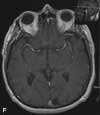

An MRI scan of the brain showed a focal low-signal area on T1-weighted images in the left occipital lobe in the area of the optic radiations. This area became uniformly more hyperintense in signal on T2-weighted images (E). No enhancement was seen after gadolinium-contrast dye injection or on diffusion-weighted imaging (F). These findings were consistent with an old left occipital ischemic infarction, which caused the right homonymous quadrantopsia. The infarction may have resulted from ischemia following blood loss during the farming accident, or it may have occurred during the protracted recovery period. Interestingly, the patient's recollection was that the vision loss had occurred in the superior left visual field and that he had recovered his vision completely.